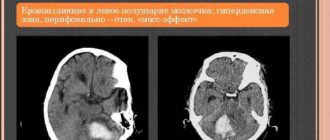

Инсульт мозжечка (мозжечковый инсульт): причины, симптомы, восстановление, прогноз © А. Олеся Валерьевна, к.м.н., практикующий